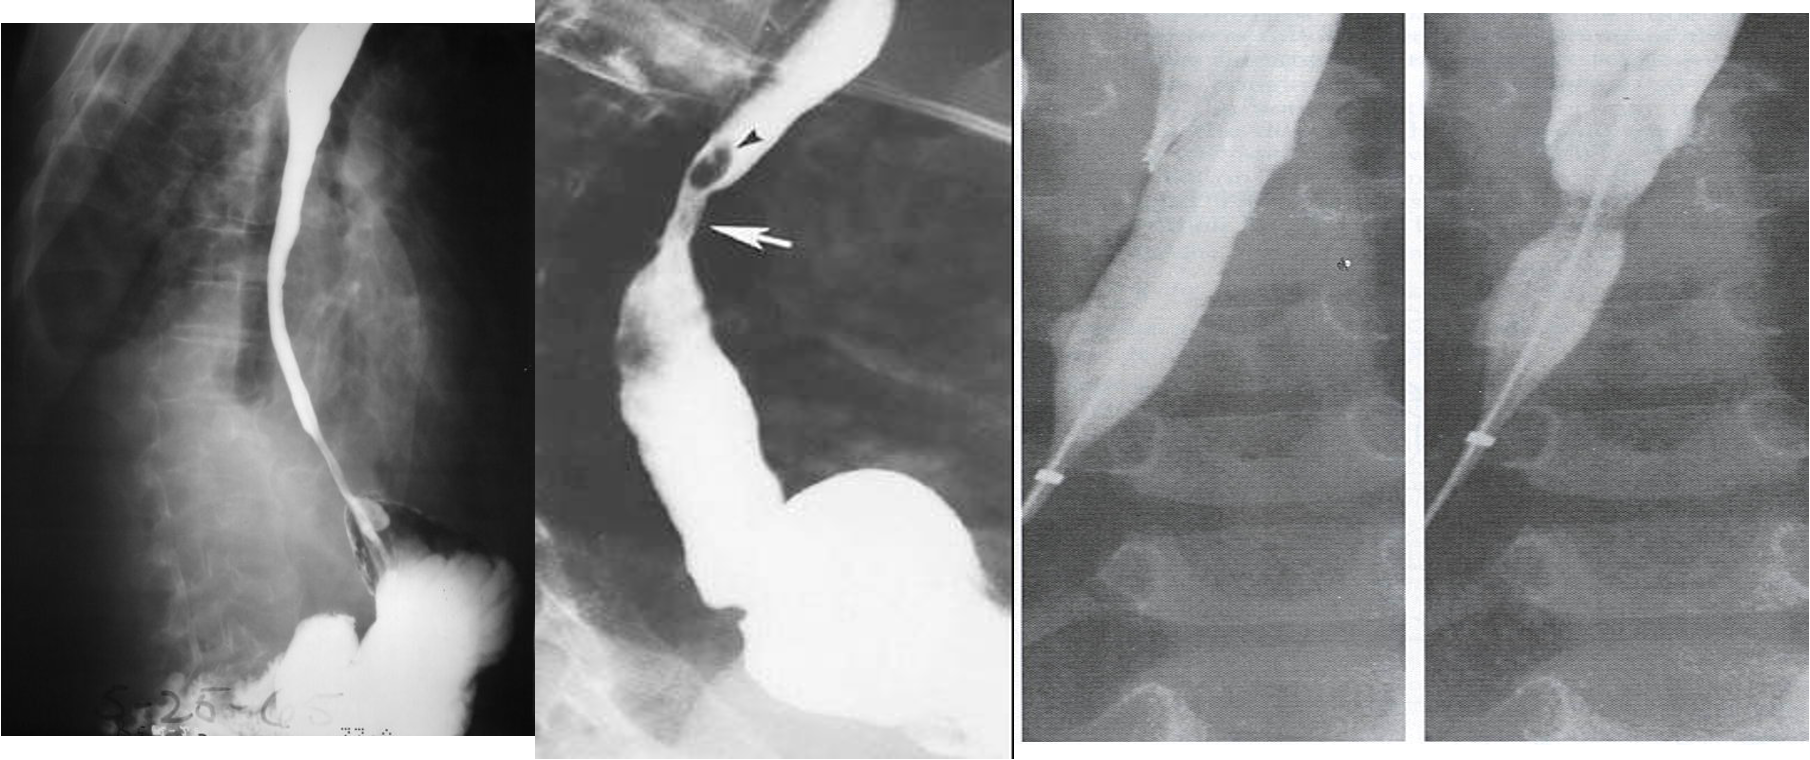

- Cicatrization stage: Dysphagia

- Dilatation and surgical repair for the stricture